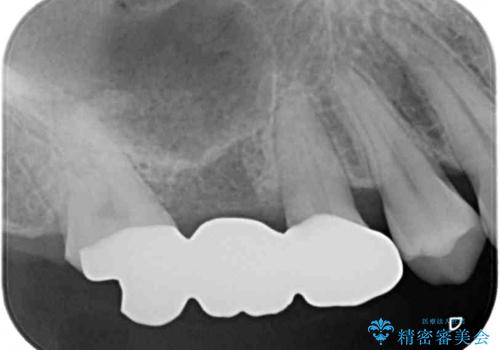

外科処置を回避するためにブリッジ治療を選択されたそうですが、頻繁に脱離するので、欠けた部分のクラウンの作り替えと、欠損部のインプラント治療を行うこととしました。

最後方歯は、クラウンを維持するための高さが不足していたため、インプラント処置の際に歯冠長を延長する手術を併用し、維持力を増すこととしました。

上顎洞までの骨高さが低いケースでしたが、ショートインプラントと骨圧縮機能を持つドリルの使用により、上顎洞底挙上を行うことなく、インプラント治療を行うことができました。